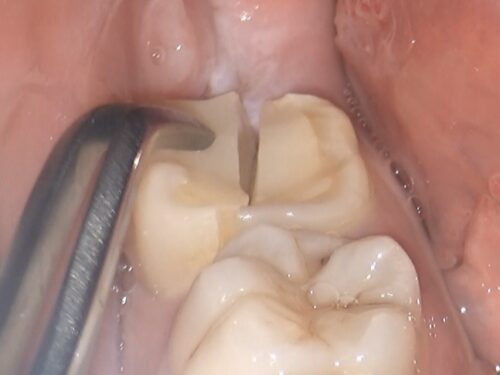

割れた破片を取り除いた直後の状態です。

骨の中まで割れていたことが確認できます。このような深い破折の場合、通常は抜歯が必要となります。